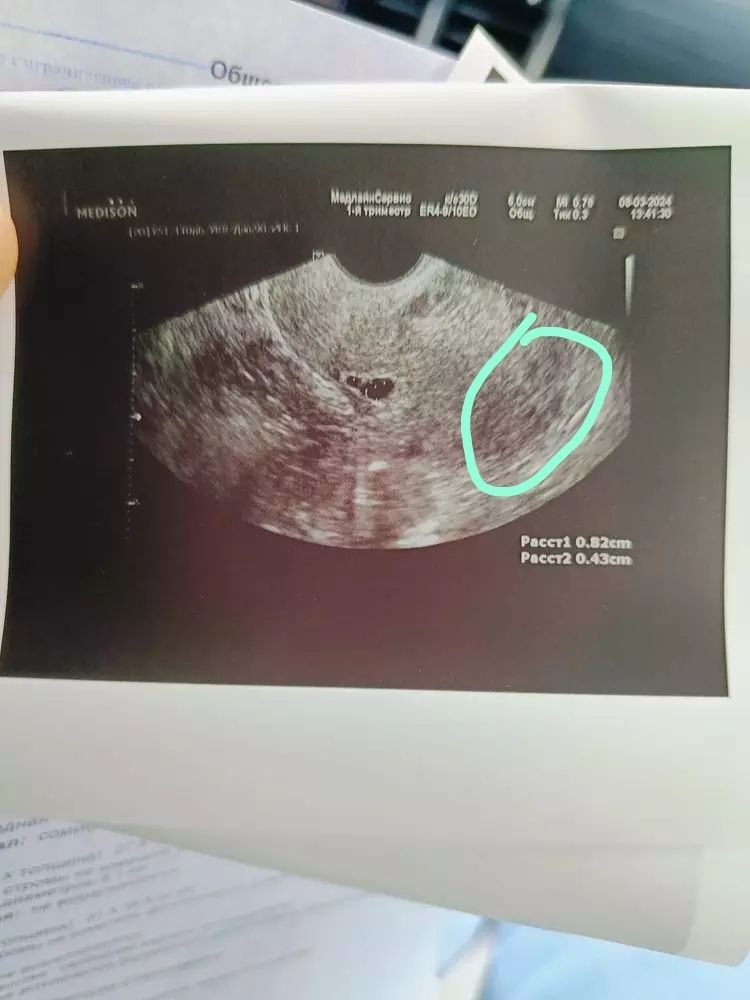

Ситуация .Беременность 5 нед 5 дней.

На узи в 5 нед 2 дня пя не нашли, но обнаружили нишу в рубце, которой никогда не было, тут закрались сомнения. В 5 нед 4 дня пошла в мёд центр, ПЯ обнаружили, но в нижнем маточном сегменте в области рубца) у меня 3 КС) узист вобще написала заключение - "эктопическая беременность в области рубца? '😞 Кто сталкивался? Чем закончилось? Я